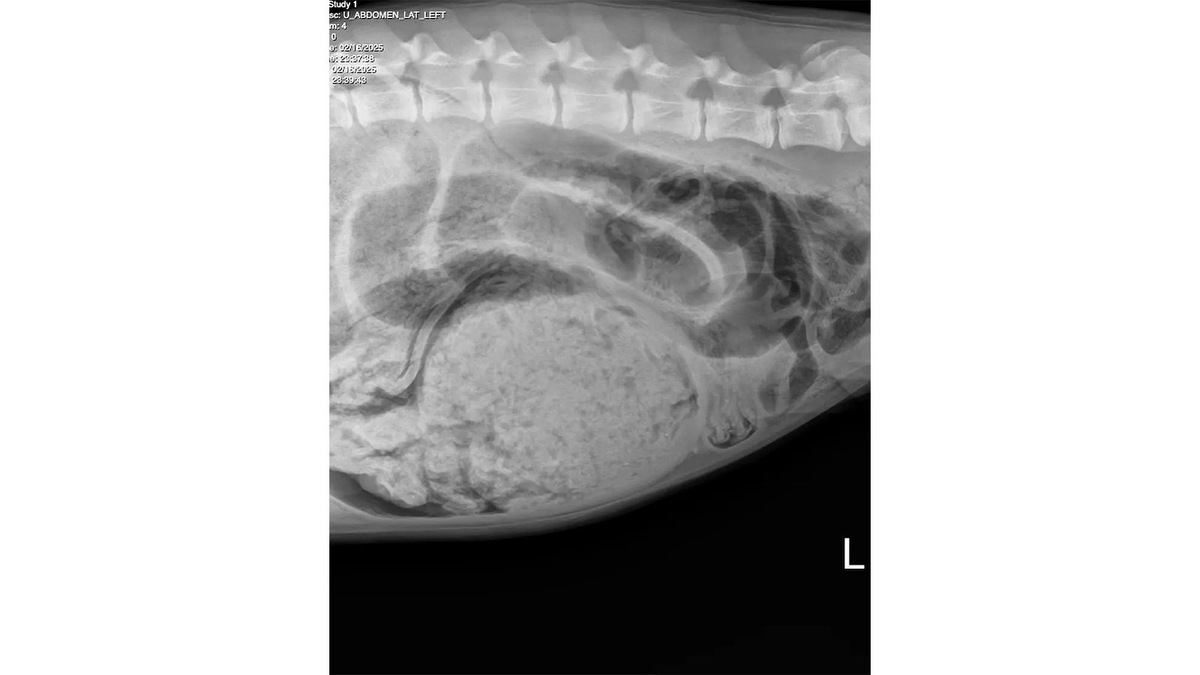

Луна, 7-месячный бернский зенненхунд, шокировала даже опытных ветеринаров, попав на операционный стол. Щенок превратил гардероб своих хозяев в обед и съел 24 носка, комбинезон, стельку от обуви, резинку для волос.

Хозяева забили тревогу, когда у Луны внезапно началась рвота, а живот стал твердым и заметно раздулся. Питомца немедленно доставили в клинику Corona Animal Emergency Center.

После рентгеновского снимка ветеринары приняли решение о срочной операции. Операция прошла успешно — медикам удалось устранить опасную кишечную непроходимость.